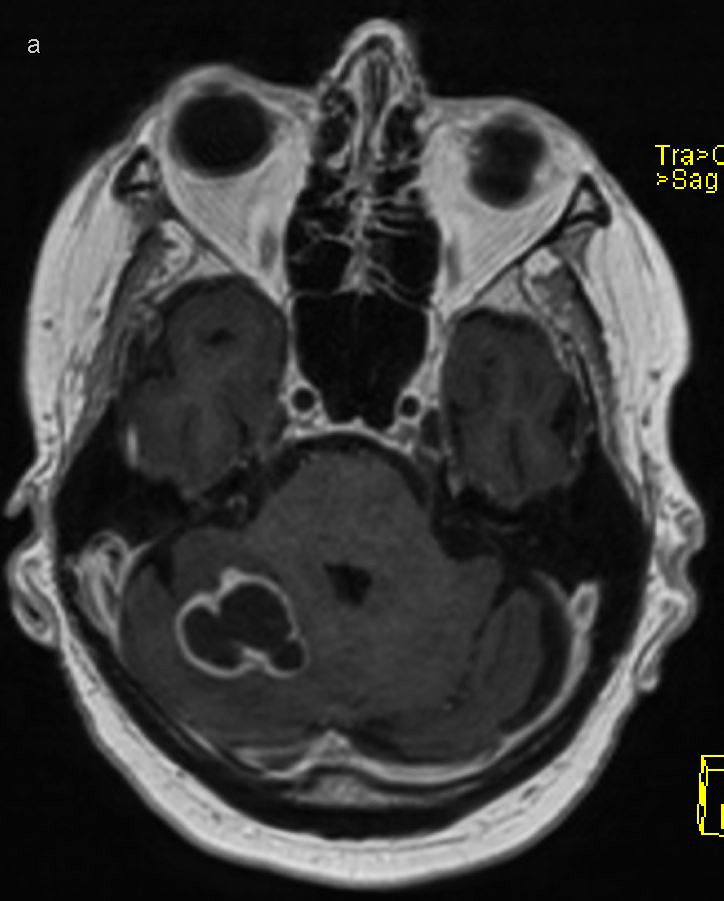

Three days after admission, the patient complained of slurred speech, and dysarthria was noted. A CT scan and MRI of the head demonstrated lesions suspected to be abscesses in the right temporal lobe and cerebellar hemisphere (Figure 2). There was no growth in four sets of blood cultures. In accordance with Norwegian and international guidelines for the treatment of cerebral abscesses, the dose of cefotaxime was increased to 4 g three times daily with the addition of intravenous metronidazole 1.5 g once daily. Transthoracic and transoesophageal echocardiography was performed to investigate a potential embolic source, which found no evidence of endocarditis. Due to deterioration in dysarthria, four days later another MRI of the head was performed, which revealed an increase in the size of both cerebral abscesses. The following day, a neurosurgeon drained the abscess for diagnostic and therapeutic purposes, with evacuation of brownish pus. The material was sent for histological examination and culture to detect bacteria and fungi. Microscopic examination of the gram-stained specimen detected no bacteria. The specimen material was also sent for 16S rDNA sequencing.

Direct spread from a local focus accounts for 50 % of cases of central nervous system abscesses, haematogenous spread accounts for 30 %, while the spread pattern is unknown in 20 % of cases (6). Drainage is recommended if the abscess diameter is greater than 2.5 cm (7). Abscesses secondary to a local focus are commonly polybacterial with oral cavity and respiratory tract microbes (8), whereas abscesses caused by haematogenous spread are typically monobacterial (6). CT is well suited as a primary diagnostic tool if intracerebral pathology is suspected, although contrast-enhanced MRI is required to differentiate an abscess from other pathology. Diagnostic aspiration and biopsy of abscess contents should be planned in consultation with a specialist in infectious diseases, neurosurgeon and microbiologist to ensure proper and rapid handling of the specimen material. The specimen material for microbiological diagnostic examination should be prepared for microscopy on a sterile slide, both for gram and Ziehl-Neelsen staining, anaerobic and aerobic culture and mycobacterial culture. If possible, the specimen material should also be provided in blood culture medium. Lumbar puncture is of little value in cases of CNS abscesses and is associated with a risk of herniation.